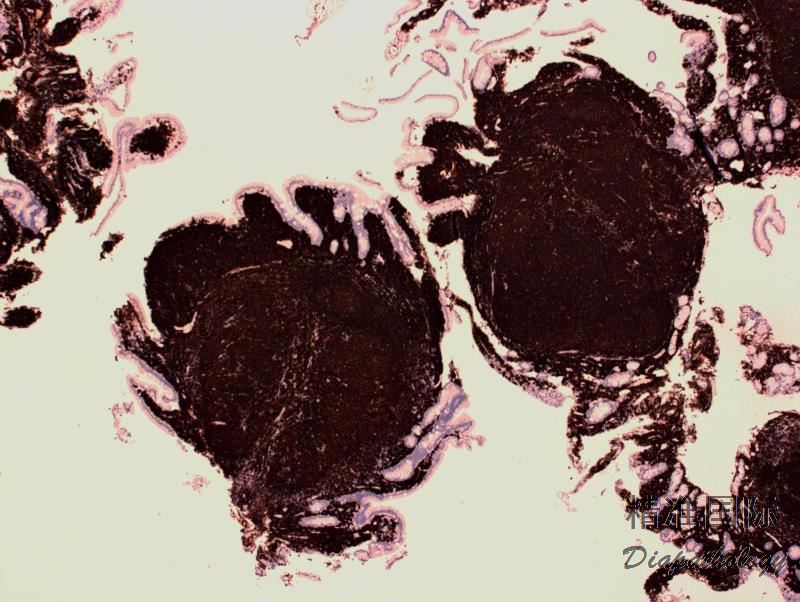

淋巴结正常结构消失,代之以紧密排例、大小和形状一致的不正常滤泡,常累及整个淋巴结或浸润到胞膜外。套区变薄、不完整、消失或极性不在。有的同时存在弥漫浸润区。偶而滤胞呈现出形状不规则或匐行性生长(类似进行性滤胞中心转化, PTGC)。

滤泡由中心细胞和不等数量的中心母细胞组成,两种细胞随机散在分布,极性和“星空”细胞消失。滤泡之间或可见浸润中心细胞。中心细胞:较中心母细胞小,核形不规则成角或有核裂,胞质少。中心母细胞:核圆形或卵圆形,呈空泡状,可见 1 ~ 3 核仁,多靠近核膜。滤泡之间或可见肿瘤细胞侵润,系中心细胞,但胞核相对规则。

免疫表型:表达 B 细胞抗原如 CD20 和 CD19,CD10+,Bcl-6+,Bcl-2+,单克隆轻链。高级别 FL,CD10 阴性相对常见。滤胞间肿瘤细胞(低级别或高级别)常弱表达或不表达 CD10,边缘区分化区域(FL 伴边缘区分化)、骨髓或外周血中的肿瘤细胞也常不表达 CD10。滤胞间区的肿瘤细胞表达 Bcl-6 也减弱。